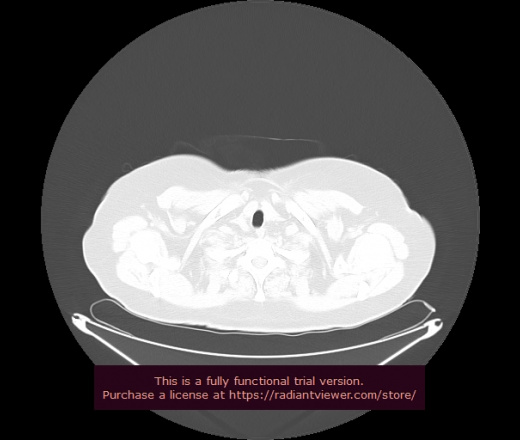

Уважаемые коллеги, если имеется интерес, сможете ли Вы спрогнозировать дальнейшее +-одинаковое течение процесса у 4 данных разных пациентов? Зацепиться где-то можно очень просто, где-то нельзя.